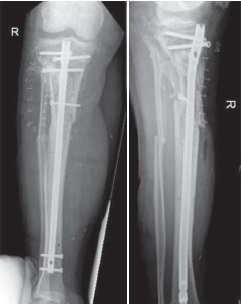

A 72-year-old male was severely injured in a road traffic accident, whereby his leg was trapped between a moving car and stationary vehicle. Plain X-rays and CT angiogram identified a comminuted proximal tibial fracture with transection of the popliteal artery and vein (Figure 1). He presented with severe hypotension, delayed capillary refill, and an absence of pedal pulses. Initial emergency treatment included fasciotomies, external fixation, and vascular primary repair conducted on the day of admission. Initially an external fixator was applied to give stability (Figure 2, 3). The patient was then turned prone and the popliteal artery was repaired primarily following a posterior approach. The patient’s post-operative period in the Intensive Care Unit (ICU) was complicated by an acute kidney injury due to rhabdomyolysis, his creatinine kinase at the time was 34.617 U/L (reference range 39-308). His rhabdomyolysis was managed by the ICU team with fluid resuscitation and diuretics, he did not require dialysis.

Figure 1. X-rays in the AP and lateral views of the right knee displaying proximal tibial fracture upon admission